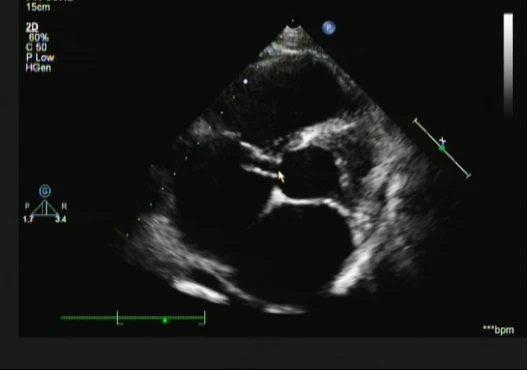

“?,这个结果……”,体型微胖但血压正常可解释不了全心增大,而右房占位或许能导致三尖瓣的偏心性返流,但高速且连续性血流频谱如何而来的呢?继续追问,患者于半个月前曾有发热病史,那么,重新仔细探查右房中的异常,我看到了--(图3、图4)

图3 图4

原来是主动脉窦瘤破裂入右房并考虑无冠窦赘生物形成。